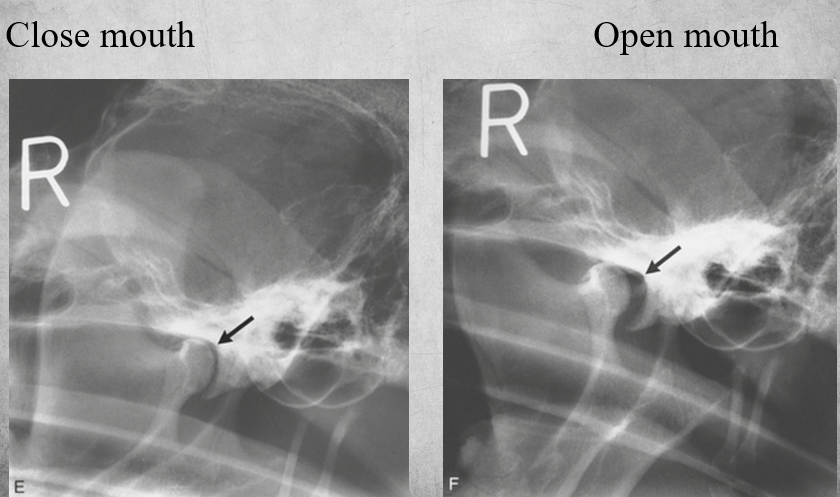

TMJ view is also called:

sagittal oblique

To view the temporomandibular joint.

Patient in lateral recumbency, nose lifted 10-30 degrees. Open mouth or closed mouth.

identify pathology

TMJ subluxation

in the closed mouth image the luxation is difficult to discern but in the open mouth view its obvious